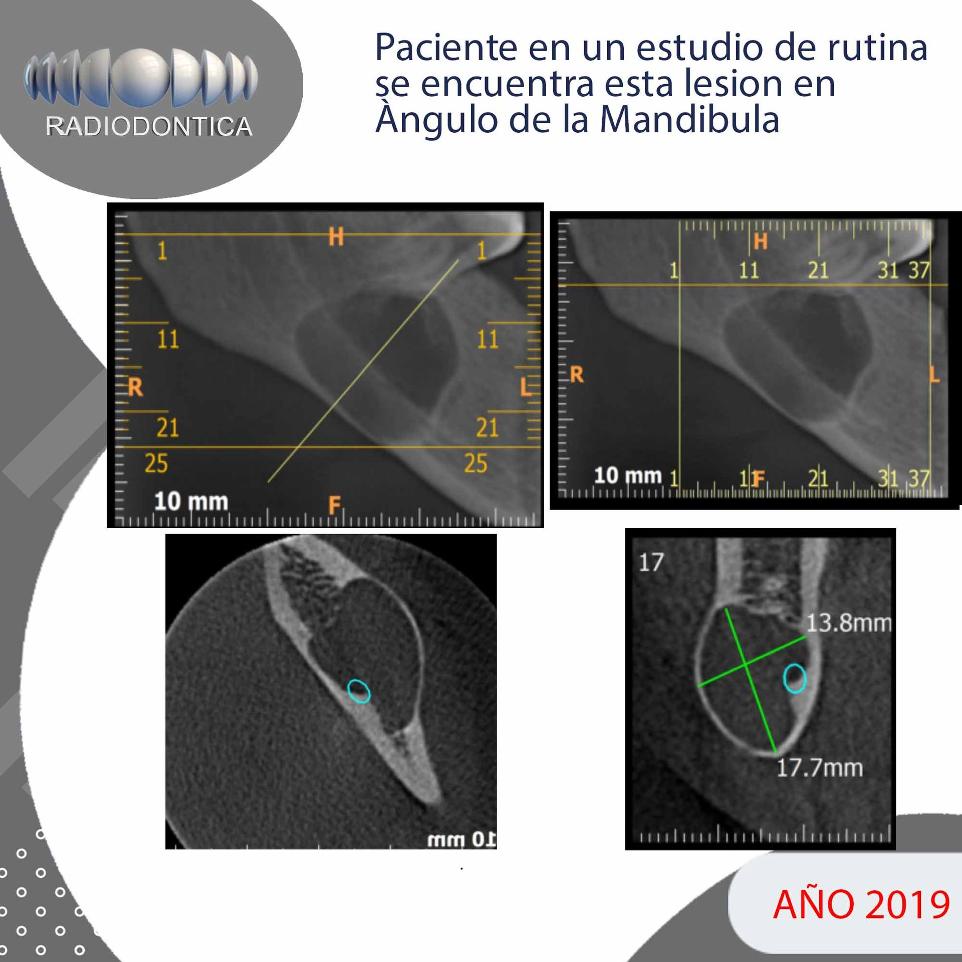

La presentación de casos radiográficos, permite la visualización de patologías que son muy difíciles de ver en la clínica, ya que muchos de ellos son hallazgos radiográficos. Además permite ver y refrescar clasificaciones y conceptos muchas veces estudiados. La presentación de los mismos no incluyen datos personales, mas que edad y sexo, que suelen ser importantes para ver la correlación entre la patología, su aparición o forma de presentación.

Caso N°